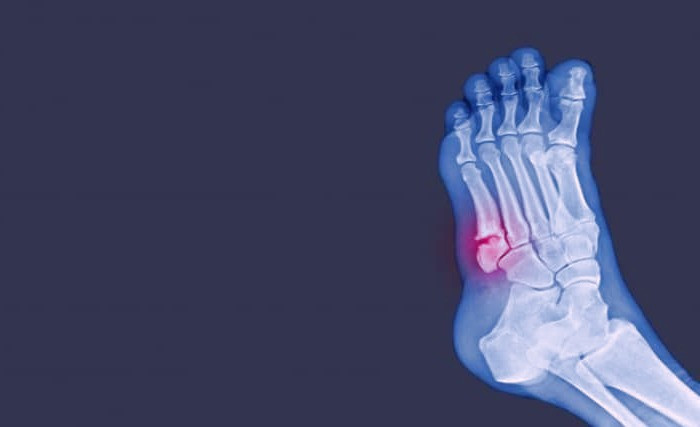

شکستگی مویی :

شایع ترین شکل شکستگی است و قسمت های شکسته شده جابه جا نشده اند و نیرویی که موجب این شکستگی شده قوی نیست.

شکستگی مویی